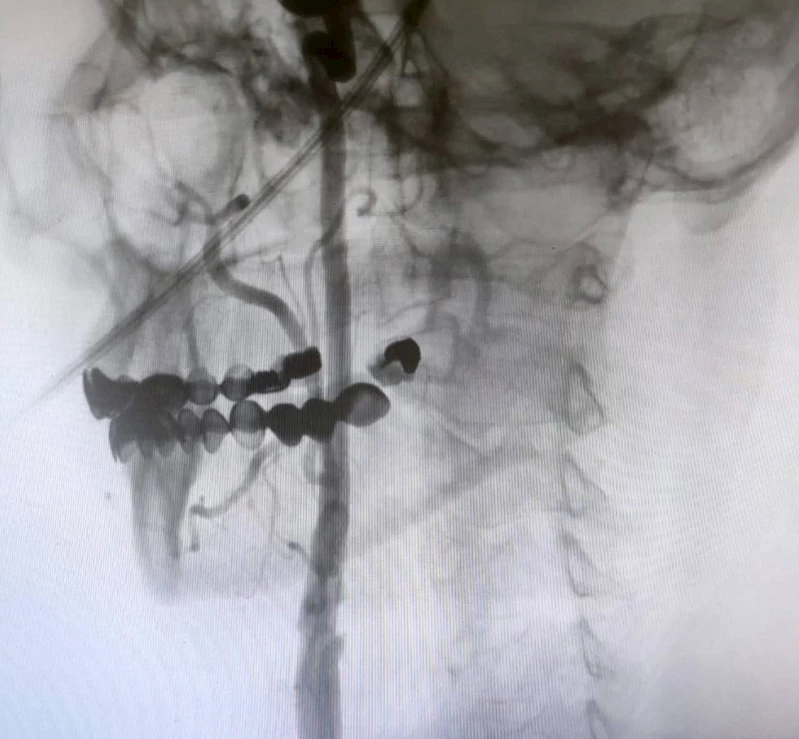

Manisa Şehir Hastanesi’nde, beyin damarlarındaki tıkanıklıklara karşı ameliyatsız stent yöntemi başarıyla uygulanıyor. Uzmanlar, şah damarındaki daralmaların inme riskini büyük ölçüde artırdığını vurgularken, bu modern yöntem sayesinde hastaların ertesi gün taburcu olabildiğine dikkat çekti.

Manisa Şehir Hastanesi’nde girişimsel nöroloji ve girişimsel kardiyoloji uzmanlarının iş birliğiyle, beyni besleyen en büyük damarlar olan karotis (şah) damarlarındaki tıkanıklıklara karşı modern tedavi yöntemleri başarıyla uygulanıyor. Uzmanlar, bu damarlarda gelişen ciddi darlıkların inme (felç) riskini önemli ölçüde artırdığını belirtiyor. Bu nedenle, felç riskini azaltmak amacıyla hastalara stentleme işlemi uygulanıyor.

Girişimsel Nöroloji Uzmanı Doç. Dr. Ezgi Sezer Eryıldız, "Beynimizi besleyen en büyük damarlar karotis damarları yani şah damarlarıdır. Eğer bu damarlarda ciddi bir darlık olursa inme yani felç geçirme riski belirgin şekilde artmaktadır ve bu riski azaltmak için stentleme işlemi uygulanmaktadır. Rutin olarak hastalarımız bu açıdan değerlendiriliyor ve bu işlemi uyguluyoruz" dedi.

Şah damarındaki daralmaları açmanın iki yöntemi olduğunu ifade eden Girişimsel Kardiyoloji Uzmanı Doç. Dr. Ramazan Gündüz ise şunları söyledi:

"Boyun damarlarını açma işlemi iki şekilde yapılabilir. Bir karotis endarterektomi dediğimiz ameliyatla bir diğer yöntem ise perkutan girişim dediğimiz stent yöntemiyle açılabilir. Biz kliniğimizde nöroloji ve kardiyoloji olarak bir konsey yapıyoruz. Damarı ciddi tıkalı olan ve buna bağlı felç geçirmiş hastalarda bu konseyde hastaya işlem yapıp yapmama kararı veriyoruz. Verdiğimiz karar çerçevesinde eğer hastaya işlem kararı vermişsek femoral arter dediğimiz kasık arterinden bir şitle 6 ya da 7 F çapında bir şitle ince bir boruyla bu damara giriş yapıyoruz ve boyun damarlarına ulaşıyoruz. Özellikle teller, filtreler ve stentlerle bu damarları açıp hastanın tedavisini gerçekleştiriyoruz. İşlem ameliyatsız olduğu için hastamız ertesi gün rahat bir şekilde problem olmazsa işlemde taburcu olabiliyor bu işlemden sonra. Bu işlemin yapılması için özellikle anjiografinin olduğu girişimsel nöroloji uzmanının ve girişimsel kardiyoloji uzmanının olduğu ve bu konuda yeterli vaka tecrübesine ve deneyime sahip uzmanların olduğu merkezler gerekir. Bunu yapabilmek için belli bir vaka sayısına ulaşmak ve bu konuda tecrübeli olmak gerekiyor. Biz de Manisa Şehir Hastanesi’ndeki girişimsel kardiyoloji ve nöroloji uzmanları olarak bu işlemi kliniğimizde efektif bir şekilde gerçekleştiriyoruz."